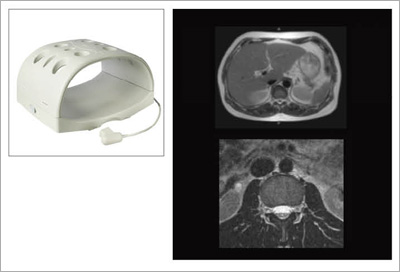

図6に,新たに開発されたOASISのRAPID Headコイルの外観と画像例を,図7に,RAPID Bodyコイルの外観と画像例を示します。それぞれ,ソレノイドコイルベースの高感度マルチコイルシステムで,すべての撮像方向で最大2倍のRAPID計測が行えます。

![]() 図7 RAPID Bodyコイルと画像例 |